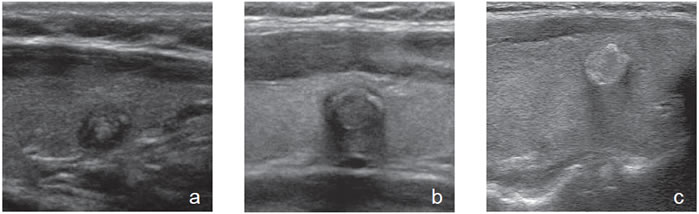

Patrón indeterminado o neoplasia simple

En nódulos con esta apariencia la etiología es impredecible, y las posibles etiologías abarcan un espectro que va desde la hiperplasia folicular (Figura 34), hasta el cáncer papilar (Figura 35a y b) y el cáncer medular (Figura 36). La probabilidad de malignidad en estas lesiones varía entre 5% a 15% en distintas series7,19-21.

Figura 34. Nódulo isoecogénico, bien delimitado, que corresponde

a una hiperplasia folicular. La ecogenicidad no es bien homogénea

y muestra algunas áreas quísticas (flecha).

Figura 35. a) Cáncer papilar isoecogénico, uniforme, delimitado por un halo fino hipoecogénico, que simula un adenoma; b) Nódulo sólido, hipoecogénico, bien delimitado (entre marcas), que corresponde a un cáncer papilar variedad folicular. C: carótida común izquierda.